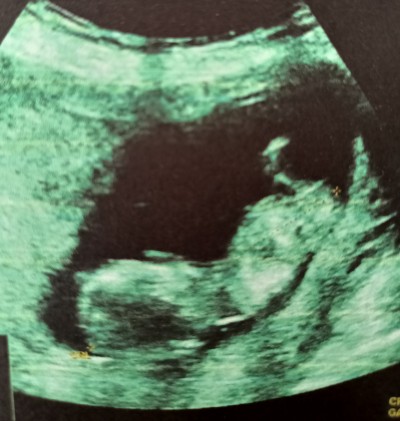

12+3 nub teorisine göre tahmin yapabilir misiniz?

Doktor 2 hafta sonra gel o zaman söylerim dedi. Nub ya da diğer teorilerden anlayan varsa yorum yapabilir mi?

Bebekte cinsel organ belli olmadan oradaki bölgenin duruş pozisyonuna göre fikir yürütüyorlar.

Erkek gibi geldi